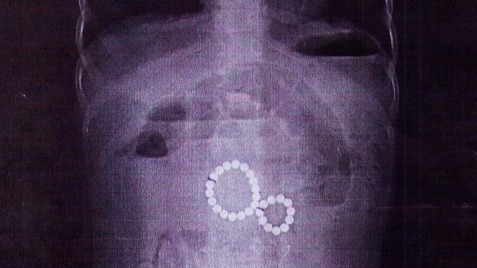

Фото: ВКонтакте / Детская областная больница Иркутск

В Иркутске двухлетняя девочка была экстренно прооперирована после того, как проглотила 29 магнитных шариков. Об этом сообщили в пресс-службе городской детской больницы.

Ребенок поступил в тяжелом состоянии с симптомами кишечной непроходимости и кровавой рвотой. Рентген показал, что магниты, попав в разные отделы кишечника, образовали опасное сцепление, вызвав внутреннюю грыжу и угрозу разрыва стенки кишки.

Хирурги извлекли все инородные предметы и устранили последствия начавшегося перитонита. В настоящее время состояние девочки стабилизировалось, она проходит восстановительное лечение.

— Этот случай — рекордный в нашей практике по количеству извлеченных магнитов. Но даже два таких шарика могут покалечить. Родители, будьте бдительны, — говорится в сообщении.